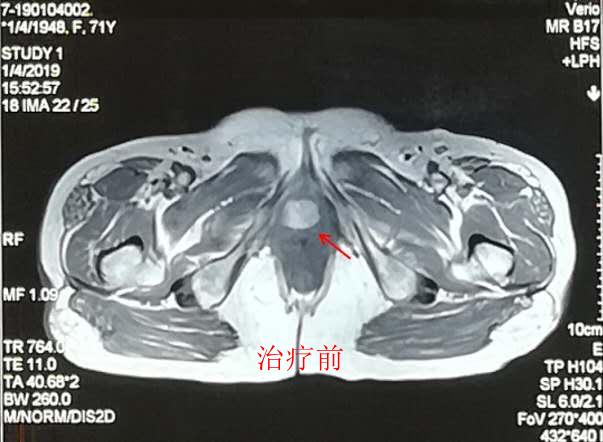

我中心一例尿道口恶性黑色素瘤重离子治疗效